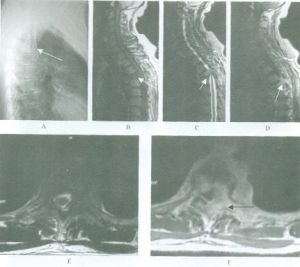

(2)間接外力交通事故,高處墜落及跳水意外時,外力多未直接作用於脊柱、脊髓,但間接外力可引起各種類型不同的脊柱骨折、脫位,導致脊髓損傷。間接外力作用是造成脊柱、脊髓損傷的主要原因。Gosolf等用猴進行多種活體脊柱損傷實驗,結論是要造成骨折脫位,除屈伸暴力外,必須要有軸向鏇轉暴力。而發生脊髓損傷的力的閾值,還受肌肉張力的重要影響。Gusta等報告46.3%的脊髓損傷患者是因剪力和扭力作用造成骨折脫位損傷脊髓,30.5%是因脊柱前中後三柱受壓損傷的結果,15.8%是因脊柱前中二柱受損結果,4.2%因過伸性脊柱損傷引起,而3.2%則是因外傷間盤突出引起脊髓損傷。近年來,人們注意到有些脊髓損傷並不伴有脊柱的骨折脫位,即外力的作用造成了脊髓損傷而沒有影象學可見的脊柱骨折脫位等異常發現。兒童的脊髓損傷多屬此種情況即SCIWORA。成人患者中有退化性脊椎病,椎管狹窄者也易發生,因易誤診應引起重視。MRI和電生理診查可為無骨折脫位的脊髓損傷提供一定診斷依據。了解外傷性脊髓損傷的具體原因,對採取相應措施預防或減少脊髓損傷的發生有重要意義。如高空作業安全帶的套用,汽車駕駛的安全帶的套用,嚴禁酒後開車以及最近汽車內防撞系統的套用等,均對脊髓損傷的預防有重要意義。

損傷程度

脊髓損傷程度的診斷即完全性損傷與不完全損傷的診斷有重要的臨床意義。脊髓損傷嚴重程度的診斷不僅是確定治療方案和判斷患者預後的重要依據,而且對客觀評估各種治療方法的實際價值有重要意義。然而,脊髓損傷嚴重程度的診斷即完全脊髓損傷的確定有時又是困難的。儘管MRI、MEP及SEP的臨床套用為脊髓損傷的診斷提供一定的客觀依據,但至今完全脊髓損傷診斷仍需依據國際統一的ASIA92標準,通過認真仔細的臨床神經系統檢查來確定。特別需要指出的是,一方面由於嚴重脊髓損傷後脊髓休克的存在,使得完全性脊髓損傷的早期診斷存在困難;另一方面,由於臨床醫生不能正確理解完全性脊髓損傷的基本定義及診斷標準,或不能準確、客觀、全面地進行神經系統檢查而使得完全性脊髓損傷的診斷不正確,導致醫生治療方案不當或預後、療效判斷失誤。國內九十年代以前有關脊髓損傷的臨床總結中,對完全性損傷報告恢復率過高,造成某些不成熟的治療方法被盲目推廣,給患者帶來不必要的損害。因此,臨床醫生必須正確理解、套用脊髓損傷神經功能分類診斷標準,正確判斷脊髓損傷的水平與程度,才能有效地進行臨床治療、康復治療及臨床研究工作。